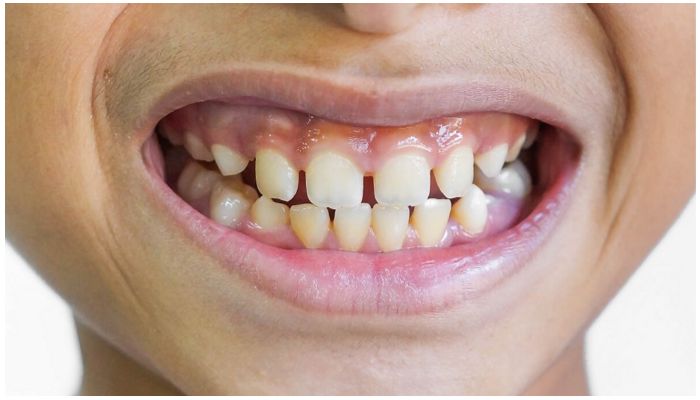

Для прогнатии характерно несоответствие смыкания зубов обеих челюсти. Верхние моляры нередко оказываются немного смещены назад, а резцы выдвинуты под углом кпереди. Клиническая картина челюстного ряда может дополняться тремами и диастемами — промежутками между зубами.

Специалист в процессе осмотра оценивает не только степень окклюзии, но и профиль лица, и симптомы патологии. Визуально клинические проявления видны на фото прогнатии — для них характерны следующие симптомы:

- расположение зубов «веером»;